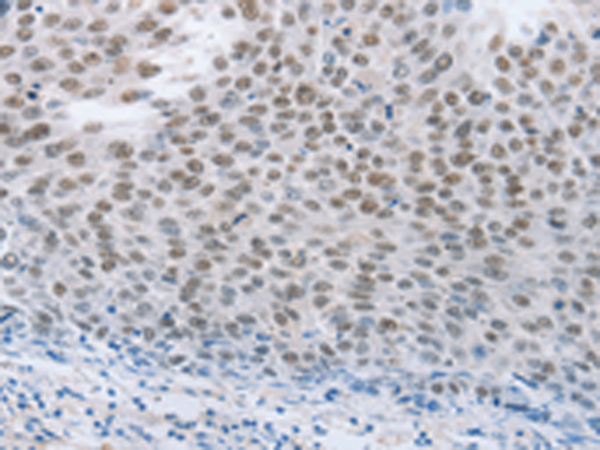

分类: 科研抗体货号: P04417别名: PD1, PD-1, CD279, SLEB2, hPD-1, hPD-l应用: IHC反应种属: Human